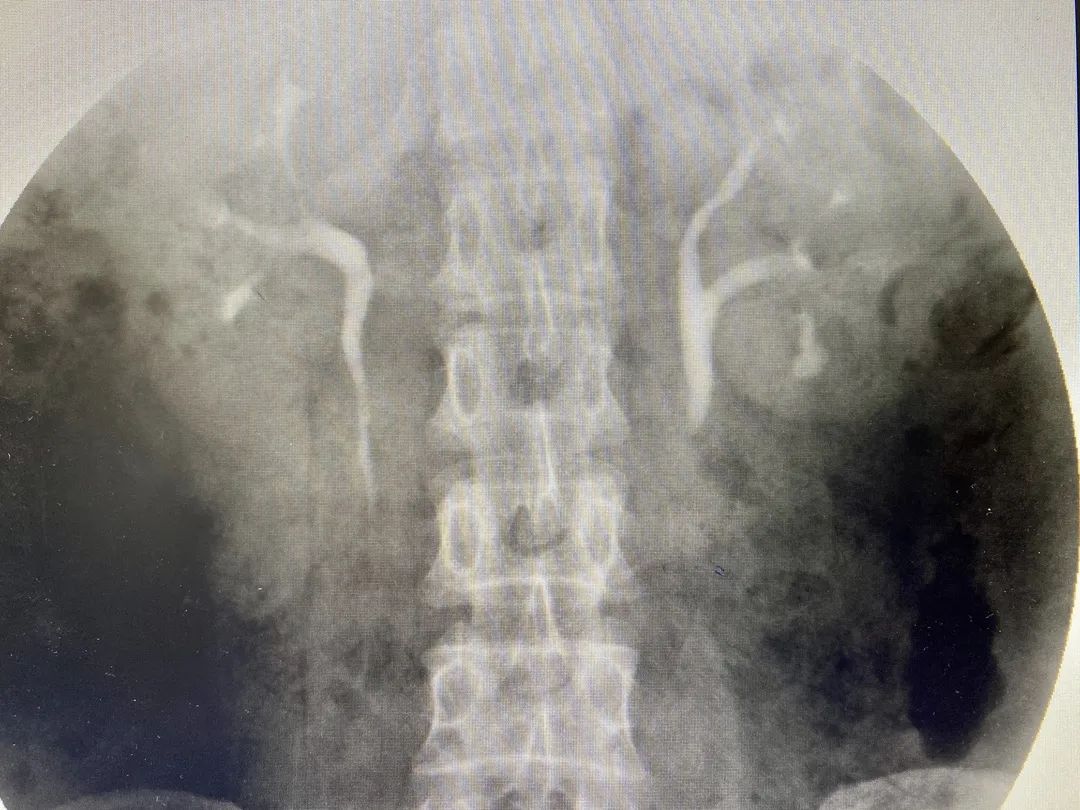

其中一名患者病情較為復(fù)雜,在術(shù)前進(jìn)行的靜脈造影中顯示,患者左側(cè)重復(fù)腎,且結(jié)石位于腎下盞,角度異常刁鉆,手術(shù)操作難度較大,要求高。